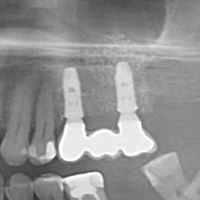

Po urwaniu narzędzia w zębie, endodonta odstąpił od leczenia kanałowego. Wykonano resekcję. Na RTG widoczne dobre gojenie tkanek kostnych, niewidoczna blizna na dziąśle.